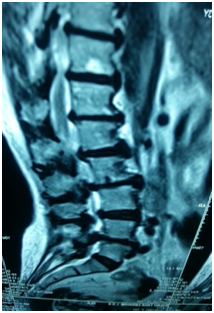

- Anterior column reconstruction with cages especially at Lumbo- sacral junction is necessary and always required to restore sagittal balance (Figure 3).

Figure 3 Flat back syndrome.